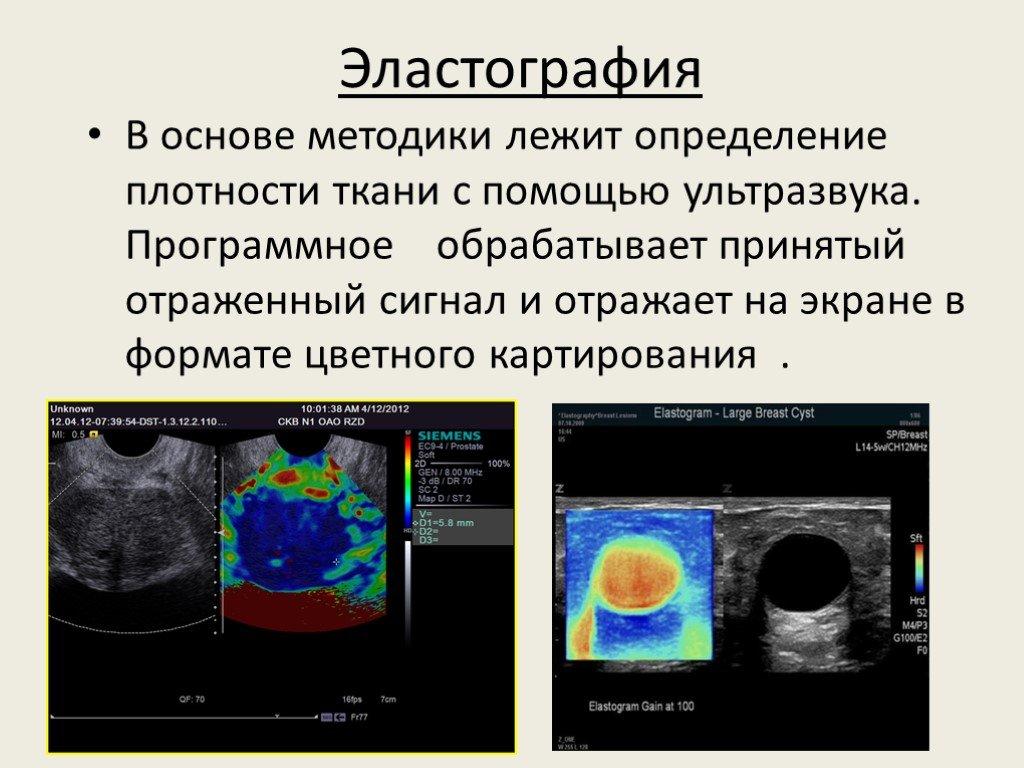

Эластометрия